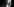

Tyrons Ellenbogen ist schwer verletzt, Splitter einer Kugel sind auf dem Röntgenbild sichtbar Bild: Carlos Javier Ortiz

Tyrone hat drei Schusswunden. Eine ungerade Zahl. Mehr Morphium, um den Arm für das Röntgenbild besser bewegen zu können. Die Schmerzmittel helfen nur bedingt. Doch das Bild muss sein. Es zeigt, dass die Splitter der Kugel in Tyrones Ellenbogen stecken. Er muss operiert werden, der Orthopäde kommt, um den Arm für die Nacht zu bandagieren, die OP kann erst am nächsten Tag stattfinden. In der Spätschicht ist das Krankenhaus schlechter besetzt, es ist zu riskant, einen OP-Saal mit einer nicht lebensbedrohlichen Verletzung zu blockieren und ein Team von Ärzten dort zu binden.